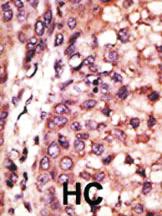

OASIS C-TERM ANTIBODY 0.1MG^ This antibody is generated from rabbits immunized with a KLH conjugated synthetic peptide (10-30 aa in length) at the C-term of last 50 aa of human OASIS. Specificity: H. Concentration: 0.25 mg/ml. Size: 0.1 mg.